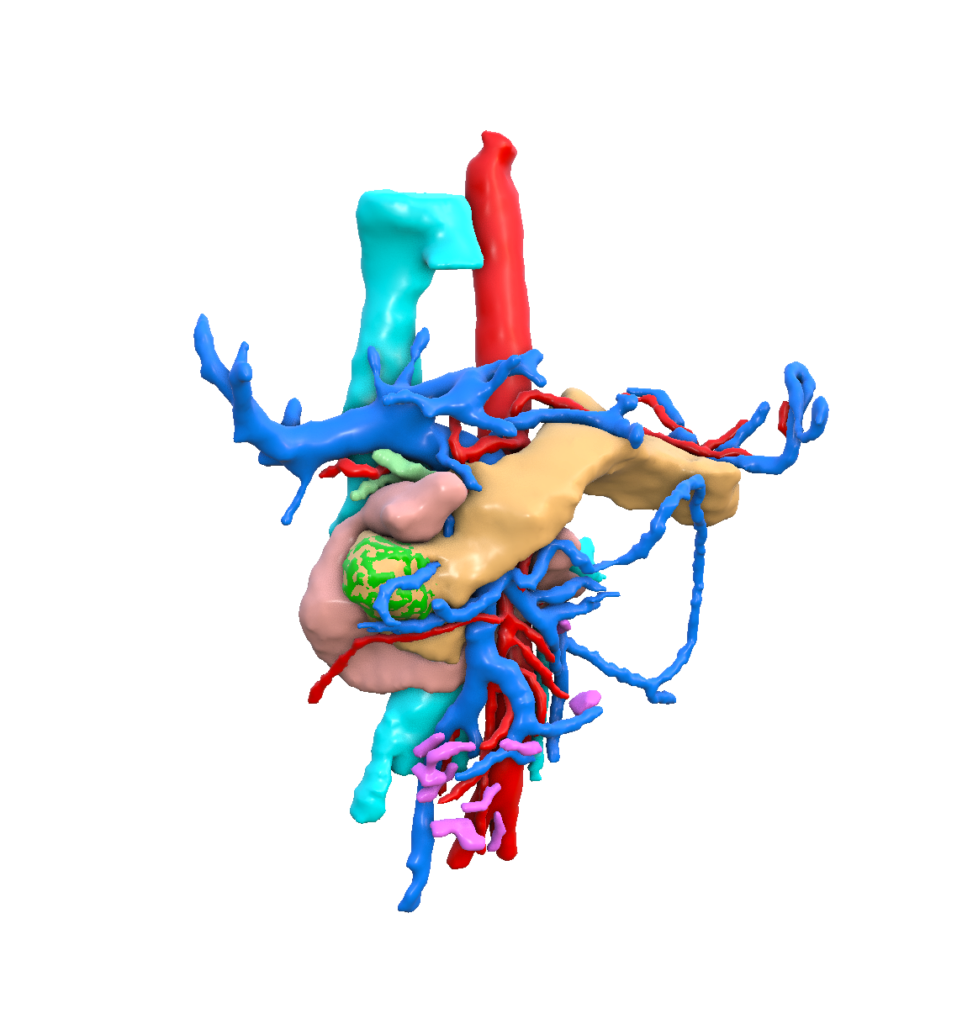

Our mission is to unlock the full potential of medical imaging data by transforming clinically validated CT and MRI images into high‑fidelity, synthetic digital human twins—enabling trustworthy, scalable, and privacy‑preserving AI development for healthcare.

To extend Visible Patient Lab’s clinically validated 3D anatomical expertise into synthetic digital human twins, enabling safe and effective AI innovation without compromising medical accuracy or patient privacy.

Artificial Intelligence and Augmented Reality are the main research axes of Visible Patient Lab.